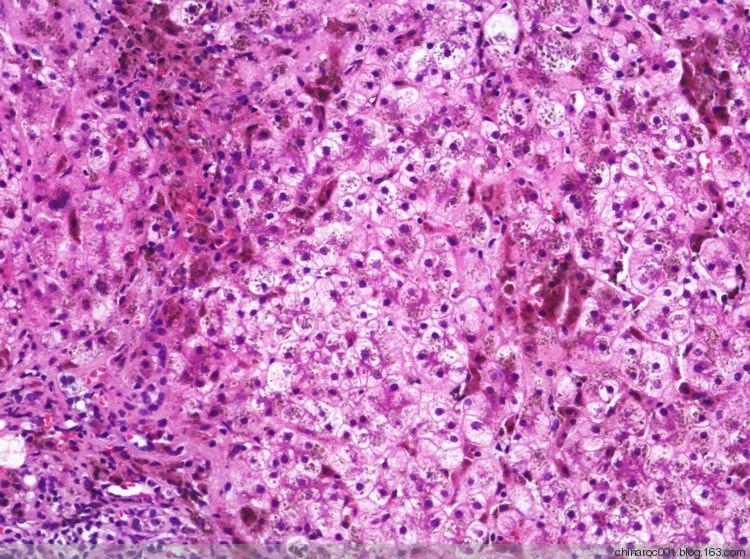

首都医科大学附属北京地坛医院病理科